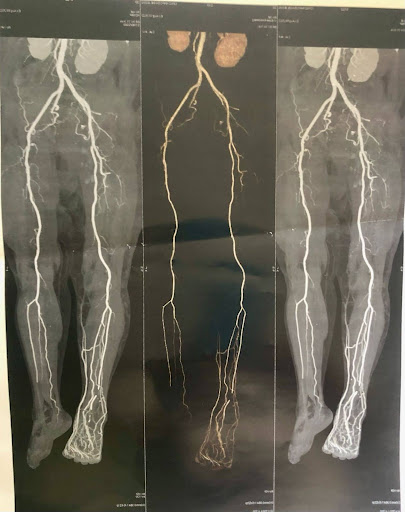

• Worsening and hospital presentation: 3 September 2022 (16 days after the injury) — foot became markedly swollen, very painful, and a plantar ulcer formed. She was taken to the emergency unit (HEU) and underwent a venous angio-CT of the lower limbs.

• Hospital recommendation: the angio-CT showed severely reduced blood flow to the right foot and extensive venous damage. The vascular surgeon recommended amputation of the right lower limb due to deficient perfusion. During this hospital stay she was diagnosed with type 2 diabetes.